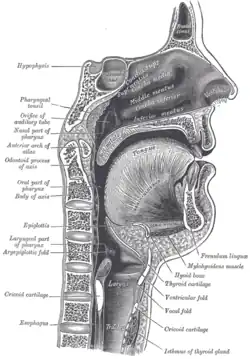

Vue bouche ouverte pour l'évaluation du grade de Malampati.

Vue bouche ouverte pour l'évaluation du grade de Malampati. Coupe sagittale du larynx et de la trachée

Coupe sagittale du larynx et de la trachée Matériel d'intubation trachéale.